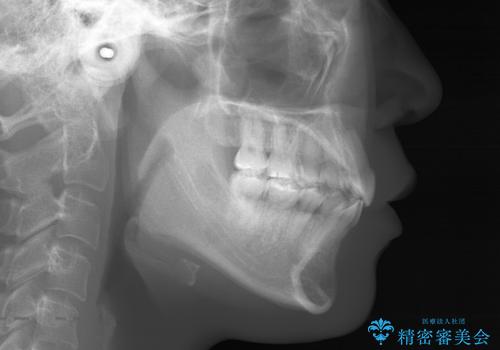

- 20代 女性

- ワイヤー(片顎舌側装置)

- 2年8ヶ月

- 治療計画

- 歯のガタつきと出っ歯感を治したいとの主訴でご来院され、ハーフリンガル装置を希望なさったため、検査を行ったうえで上下左右4番目の歯を抜歯し歯列を内側に引っ込めつつ叢生の改善を行うこととなりました。